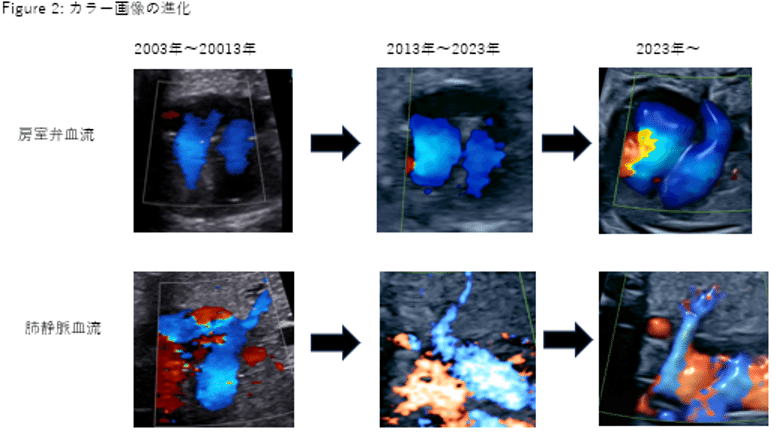

動画で見る・胎児心エコー診断 3−カラードプラーを活用した。動画で見る・胎児心エコー診断 3−カラードプラーを活用した。第3回胎児心エコーwebinar 【4ch3】完全房室中隔欠損は拡張期に。動画で見る・胎児心エコー診断。動画で見る・胎児心エコー診断 1.2.3川滝 元良DVD付 ほぼ未使用 ネーム印あり#川滝元良 #川滝_元良 #本 #自然/医療・薬学・健康